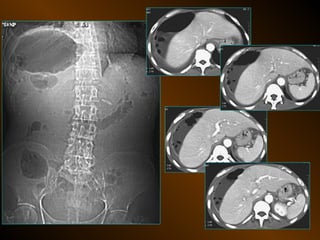

• HÌNH BỤNG KHÔNG SỬA SOẠN

• Kỹ thuật :

• Bao nhiêu phim ?

• Yếu tố kỹ thuật ?

• Tư thế nào quan trọng ?

• Cách phân tích

• 4 loại bất thường

• Chỉ định : hơi tự do

tắc ruột

sỏi niệu